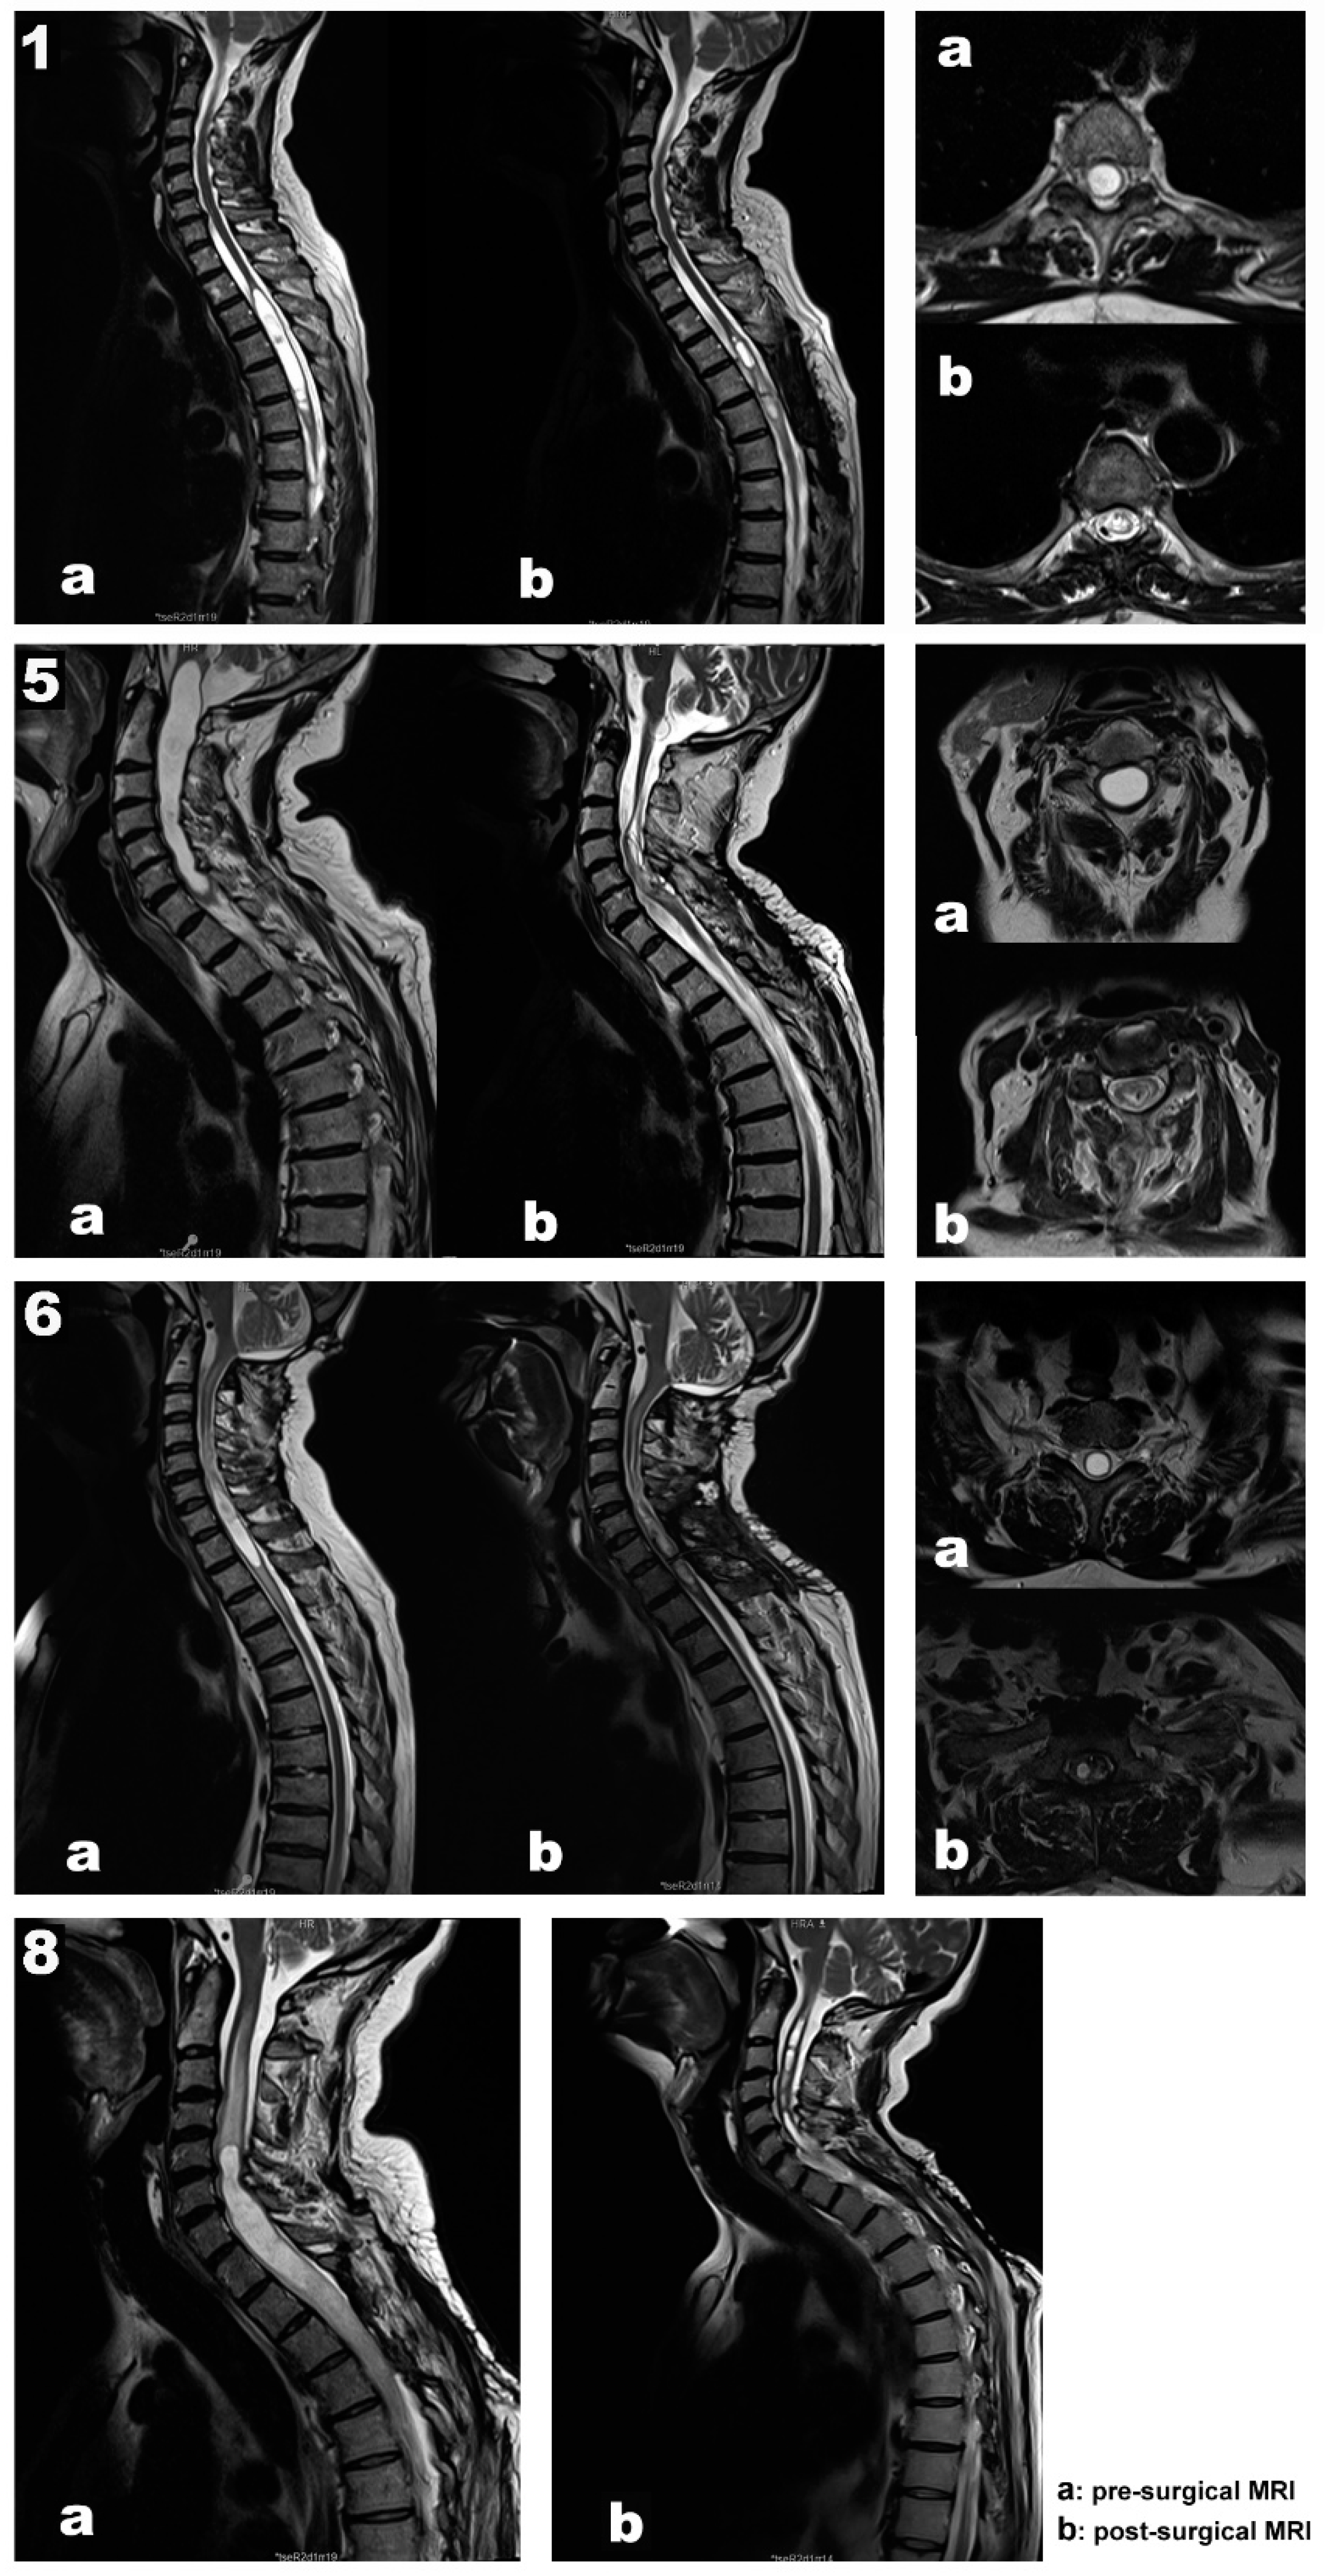

Our data support a positive and negative predictive value of 100 % for MEPs, SEPs, and EMG. In addition, in all patients, the length and diameter of the syringomyelic cavities were reduced in the follow-up MRI performed six months after surgery (Figure 1, images b).

Illustrative cases

Case 1. A 67-year-old woman, independent for daily-life activities, presented with post-traumatic syringomyelia—falling from a horse when she was 30—at the Th2-Th6 segments (Figure 1. Top panel, images a). She referred back pain of about seven years of evolution and associated loss of sensitivity and strength in the left lower extremity in the last year. At surgery, MEPs and SEPs from the four extremities were present at baseline. After laminectomy, a left DREZ myelotomy was performed at the Th4-Th5 segment. A syringo-peritoneal shunt was placed. During shunt placement, a significant reduction of more than 80% in amplitude and near-complete loss of left distal MEP (AH) was observed and reported. After slightly repositioning the shunt, the left AH MEP amplitude recovered. No changes were observed in the contralateral muscles. Bilateral PTN SEPs remained stable (Figure 2). The patient showed symptoms of improvement postoperatively, and the neurophysiological test showed no damage to the CST (Table 2).

Case 5. A 70-year-old man presented with syringobulbia and central SC edema, which extended to Th1, associated with a spinal hemangioblastoma (Figure 1. Second panel, images a). Clinically, the patient presented with progressive proximal paresis in the four extremities, especially the right upper extremity. In addition to the neurological impairment, neurophysiological tests showed acute radicular/anterior horn affectation. A moderate-severe axonal loss was associated with the right C8-Th1 segments, with minimal repercussion on the left side at the same level. Also, we found mild involvement of the DC pathway for the upper limbs and right lower limb and mild impairment of the pyramidal tract for the left lower limb, with normality for the right lower limb and both upper limbs.

Case 6. A 61-year-old man presented a Chiari malformation type 1 that required posterior fossa reconstruction 13 years ago. Even though a new pseudo cisterna magna was created, the MRI showed persistent cervical-dorsal syringomyelia (Figure 1. Third panel 3, images a). Two years before surgery, the patient presented clinical deterioration, with spastic paraparesis, hyperreflexia in both lower extremities, positive Babinski sign, and a dorsal column syndrome with positive Romberg. In the last few months, the patient used a wheelchair to move around both inside and outside the home, having difficulties to maintain standing balance. In the left upper limb, there was global paresis with a muscular strength of 3 out of 5, more accentuated in the extensor muscles of the hand and fingers with marked amyotrophy of the thenar and hypothenar eminences. MEPs and SEPs from the four extremities were present at baseline. The patient’s positioning was monitored, establishing prepositional MEP and SEP baselines while the patient was supine. No significant changes were observed in the prone position. A laminectomy at the C7-Th1 level was performed. After the dura mater was opened, the left DC was identified using the DCM technique and no response was obtained when the DREZ was stimulated. In addition, the left C8 dorsal root was stimulated and identified with monopolar hand probe. A 4 mm lateral myelotomy was performed in segments C7-Th1 at the level of the left DREZ, and a syringo-pleural shunt was placed. SEPs and MEPs were stable throughout the procedure and no EMG discharges were observed. In the postoperative period, the patient’s paresis of the left upper extremity improved, presenting better muscle balance in the extensors of the hand and fingers.

Case 8. A 48-year-old male presented with recurrent post-traumatic holo-cord syringomyelia (Figure 1. Bottom panel, image a). The patient had a traffic accident in 2012, presenting incomplete acute SC injury with sensory level L3 right/Th11 left, motor level L4 right/L2 left, ASIA D. Initially, the patient underwent posterior fusion at Th11-L3 segments in 2012. However, he developed secondary syringomyelia that required several surgical treatments, with significant clinical deterioration since September 2014. Previous surgeries included a Th6-Th8 DREZ myelotomy for intramedullary stent placement in 2016, a DREZ myelotomy at C2-Th4 for a syringo-pleural shunt in 2017, and a left DREZ myelotomy at C7-Th1 for syringo-peritoneal derivation in 2018 (Case 3 in Table 1). Over the last years, the patient reported neuropathic back pain, thermo-algesic sensory alteration in the left hemithorax and hemiabdomen, and progressive deterioration of strength and sensitivity in the extremities. Before surgery, the patient experienced progressive clinical worsening, with bilateral upper extremity weakness, more prominent in the distal muscles. The MRI showed progression of the syringomyelic cavity with greater extension at the cranial level, reaching the medullary obex. The patient also presented marked post-laminectomy cervical-thoracic kyphosis, so it was decided to correct the deformity and replace the syringomyelic shunt in the same surgery (Case 8 in Table 1).

Figure 1. Preoperative (a) and follow-up (b) magnetic resonance image scans from each illustrative case (1, 5, 6, and 8). Sagittal and axial view of the syrinx.